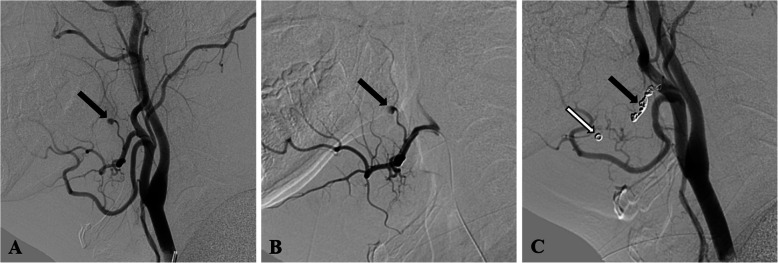

Results: The angiogram revealed pseudoaneurysms in the ascending palatine artery in two patients, the facial artery in one patient, and the lingual artery in the other patient. Two patients were treated with endovascular embolization using n-butyl-2-cyanoacrylate (NBCA) glue, one patient was treated with coils, and one received a combination of coils and NBCA glue for embolization. All procedures were successful, with no clinical complications or rehemorrhage reported.